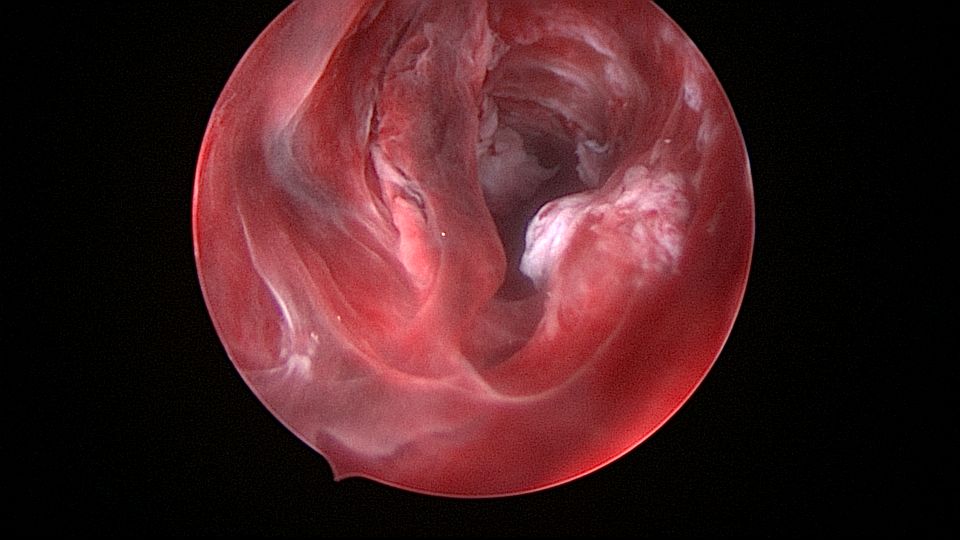

患者54岁,G2P1,顺产1次。安环26年,绝经1年,外院取环失败,子宫穿孔。宫腔镜术前B超提示子宫前位,盆腔未见异常。子宫极度前倾前屈位,宫腔下段后壁偏右穿孔,宫腔镜进入盆腔,见肠脂垂,未见积血,宫腔镜退出盆腔,寻找节育环。手术大部分时间在寻找宫颈内口和宫腔方向,在子宫穿孔的左上方找到宫颈内口,宫腔镜艰难进入宫腔,异物钳取环就迎刃而解了,取出一枚O型环。